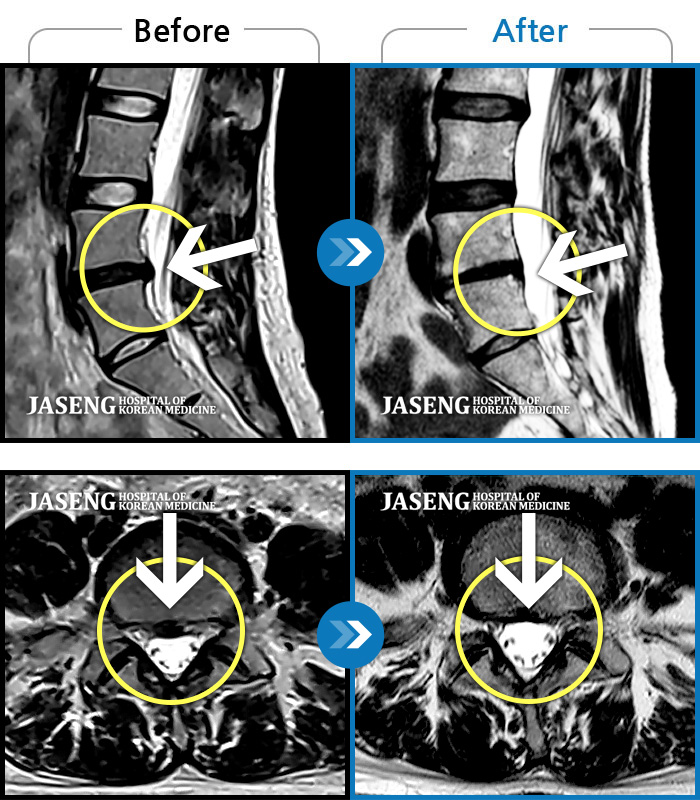

허리디스크

강남 · 강만호 원장

허리 통증 및 왼쪽 다리 근력저하 감각저하로 일상생활이 불가능했습니다.

촬영시기

2024.05.18 ~ 2025.12.03

2025.12.19

조회수 101